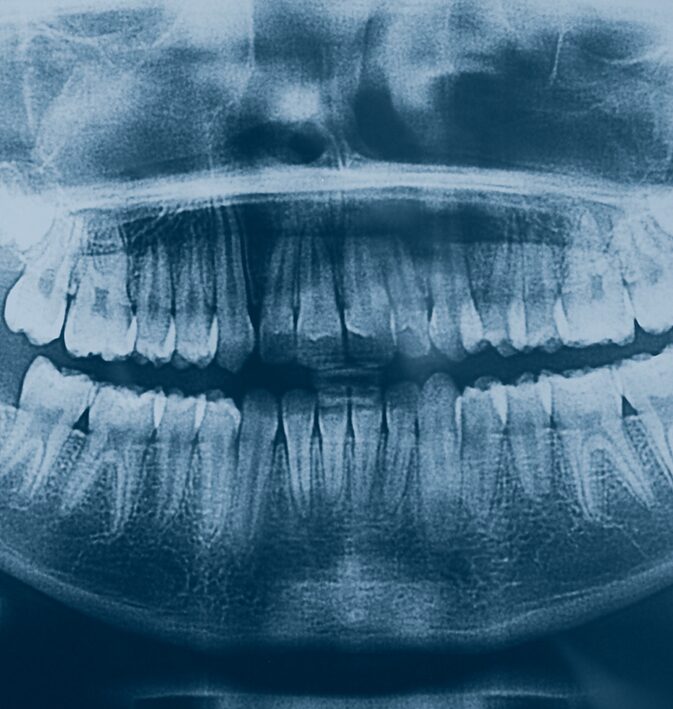

• Rapid examination and digital X-rays